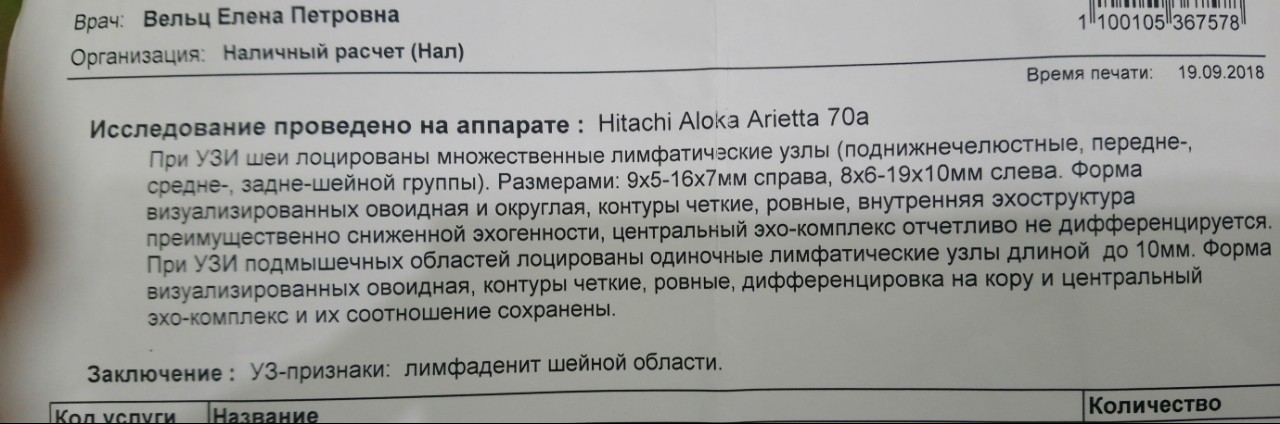

УЗИ лимфоузлов при лимфоме Ходжкина

Раздел: Образы вокруг